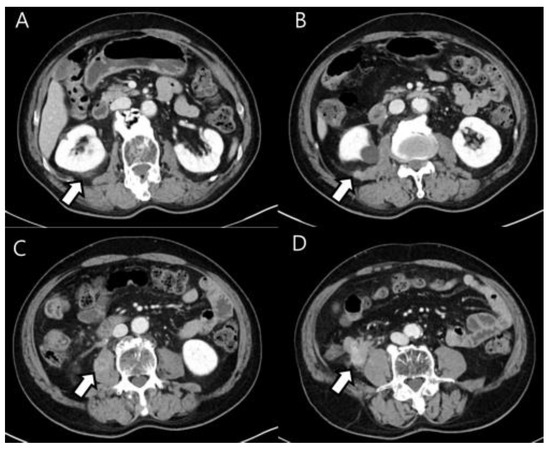

Figure 1.

Axial, intravenous, contrast-enhanced CT scan of the abdomen (A–D) reveals an infiltrative-enhancing soft tissue mass in the terminal ileum. It also shows several enhanced soft tissue nodules in the right Gerota’s fascia, transversalis fascia, posterior pararenal fascia and right psoas muscle.